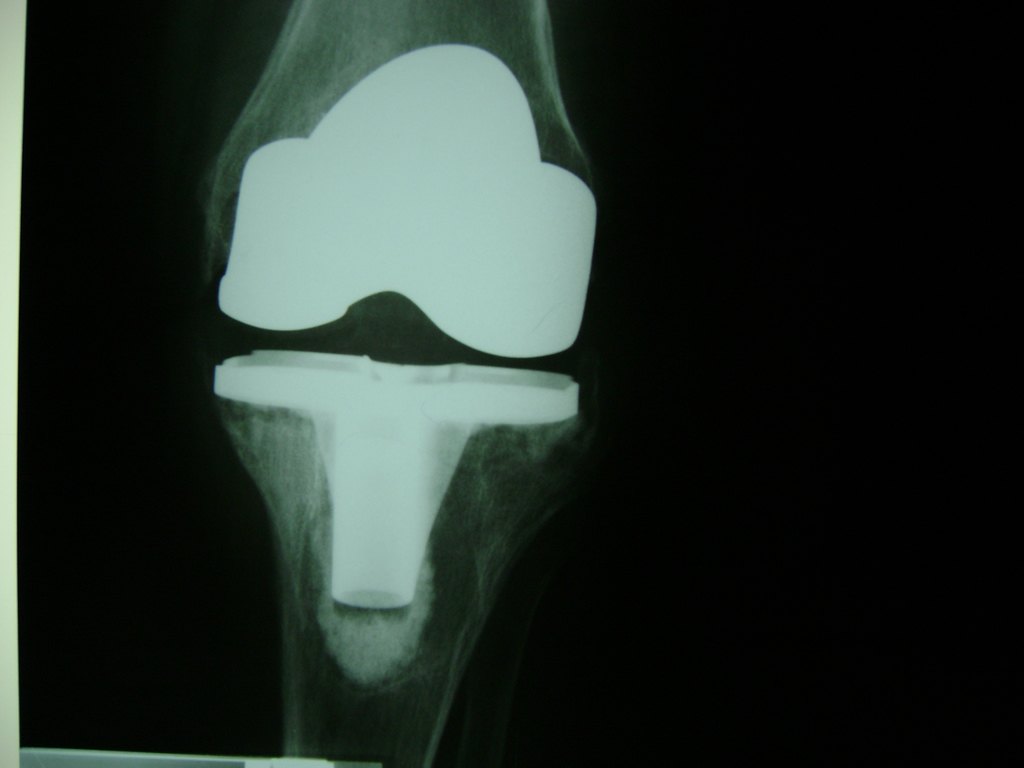

Fémur - Rodilla

La artroscopia de rodilla es un cirugía en el cual la estructura interna de la articulación es examinada ya sea para realizar un diagnostico o para realizar un tratamiento, este procedimiento se realiza utilizando un instrumento parecido a un pequeño tubo llamado artroscopio.